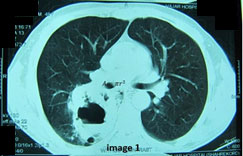

We report a case of FSGS (tip lesion) with nephrotic syndrome and acute renal failure that complicated with pulmonary and brain abscesses and was under immunosuppressive therapy. The patient was a 48-year-old man who was admitted for evaluation of azotemia. There was a history of decreased urine volume in recent days. He presented with BP=160/100 and 3+ leg edema on physical examination. He did not have any history of recent sore throat, hypertension (HTN), oral ulcer, arthralgia, photophobia, skin rash or family history of renal disease. Urinlysis showed 3+proteinuria and 2+hematuria. Serum creatinine was 2.3 mg/dl, blood urea nitrogen=32mg/dl, serum albumin=2.4g/dl, triglyceride=295mg/dl, cholesterol=320mg/dl, Hb=13g/dl and 24 h urine protein was 6580 mg/day. Other laboratory findings were unremarkable. He was oliguric and the serum creatinine gradually increased to 6.8 mg/dl during the next few days. Microscopic urine sediment showed many muddy brown coarse granular cast, dysmorphic RBC and fatty cast. Because of elevated serum creatinine and uncontrolled hypertension and volume overloading, hemodialysis was started and after blood-pressure control (by amlodipine 10mg/day, prazocine 5mg/bid, metoprolol 50mg/bid), renal biopsy was done. The results of serologic examination including ANA, anti-ds DNA, C3, C4, CH50, HBS Ag, HCV Ab, HIV Ab, Cryoglobulin, Anti GBM Ab and ASO were normal. Renal biopsy showed focal segmental glomerulosclerosis (tip lesion type) as well as acute tubular necrosis. Corticosteroid pulse (methyl prednisolone 1000 mg/day) was prescribed for three days and continued with 60 mg prednisolone/day. Conservative management of metabolic acidosis, hyperlipidemia, anemia and hypocalcemia was continued. after hemodialysis three times daily (HD), urine output increased and serum creatinine decreased gradually to 1.5 mg/dl and his oedema decreased to 1+ after two weeks of admission, so he was discharged and prednisolone was tapered gradually to 20 mg/day during 4 months. Because serum creatinine was increased, cyclosporine 100 mg/bid was started and after four weeks, serum creatinine reached to 0.8 mg/dl and urine protein was 740 mg/day. Six weeks later, he suffered from productive cough and shaking chill and fever. Chest x ray and chest CT scan revealed right side pulmonary abscess [Table/Fig-1]. BK (Bacille de Koch) smear of sputum was negative. Treatment with ceftriaxone 1g/bid/IV infusion and clindamycin 600mg/tds/IV infusion was prescribed and after four days, fever disappeared. After two weeks of parenteral treatment, he was discharged and oral antibiotics with Amoxicillin-clavulanate 625mg/TDS continued for four additional weeks, and the, second lung CT scan was near normal [Table/Fig-2]. Cyclosporine dose was reduced to 100 mg/day and serum creatinine remained 1.5 mg/dl. After three months he was again referred to clinic with dysarthria and right side face deviation and hence was admitted. A large round mass like lesion was detected in his right side brain CT scan and MRI [Table/Fig-3]. Differential diagnosis was: bacterial, nocardial or fungal brain abscess, brain lymphoma, and atypical brain tuberculosis. Tuberculin standard test (TST) was <5mm and bone marrow aspiration was normal. The patient was with fered to undergo astreotaxis biopsy of brain lesion but because of his reluctance, empirical treatment with parenteral penicillin 4 million unit /q4hr + metronidazole 750mg/tds + trimethoprim sulfametoxazole 800/4000 mg/q24hr, IV infusion, were started. After two weeks of treatment, severity of dysarthria and size of brain lesion decreased [Table/Fig-4,5]. This parenteral antibiotics regimen continued for eight weeks in hospital and due to high suspicious of brain Nocardiosis, oral trimethoprim sulfametoxazole, was continued for additional eight months. Also, treatment of FSGS was continued with prednisolone 20 mg/day, losartan 25mg/bid, furosemide 40mg/bid, prazocine 5mg/bid, atorvastatin 20mg/day, ASA 80 mg/day and diltiazem 30 mg/bid. After 10 months of treatment, he is well without any focal neurologic abnormality, and near normal brain MRI. His serum Cr is between 0.9 mg/dl and urine protein is 625 gm/day.

Right pulmonary abscess before treatment